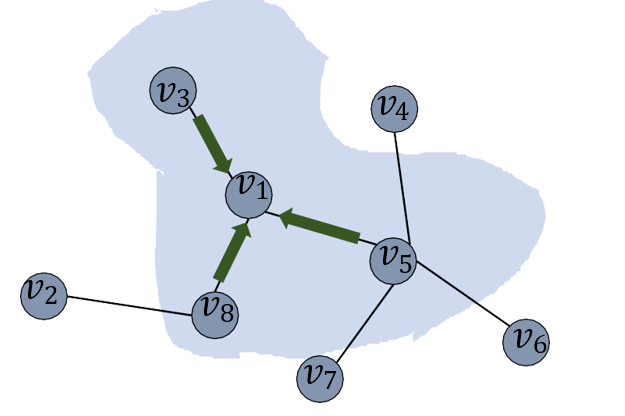

GCN in Fig. 5 (see detail structure in Fig. 7) is to extract the spatial features of topological graphs by using the topologically-stable relationship information. Meanwhile, after convolutional graph operation, pixels feature belonging to the same class in semantic segmentation will be close to each other in the feature manifold (see Fig. 6).

We multiplied the feature map with the corresponding transpose as input of the GCN block. Global features will be generated by two layers of GCN blocks (see Fig. 7), while the global topological relationship of graph structure-based features (see Fig. 6) is obtained. The final feature map is fused by adding (see Fig. 5) the encoder output and the global relationship node feature together.